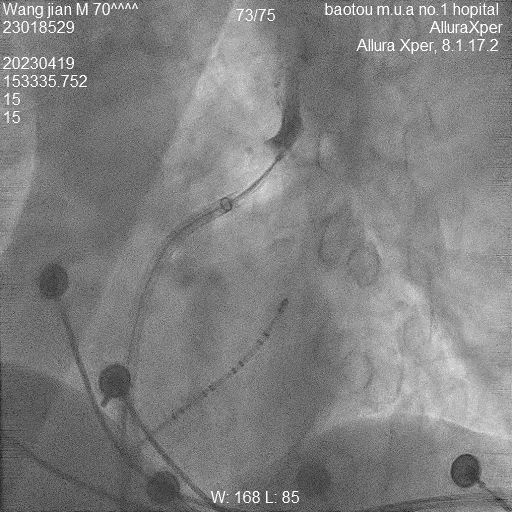

据了解,患者王先生今年70岁,房颤病史已经持续了1年,尽管一直以来坚持规律用药,但仍然觉得心悸、气短,活动耐量明显下降。10多年前王先生曾因“室上性心动过速”接受过传统的射频消融手术治疗,由于各种原因,王先生术中感觉不适,因此非常抵触这类治疗方式。针对该情况,包医一附院心内科三病区医护团队经过认真评估,判断王先生也同样适合“分段式肺静脉前庭冷冻消融”,该术式与传统射频消融术相比,患者体验明显舒适,术中几乎毫无痛感。此外,因该术式同时干预参与房颤形成的肺静脉前庭,扩大了消融部位,使得术后房颤复发的概率大大降低,极大提高了手术的成功率,是目前更为先进的冷冻消融术式。手术经过一小时顺利完成,王先生的心脏如期恢复了正常的窦性心律。